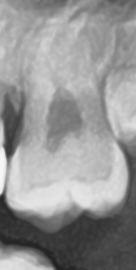

27번치아 교합면에 충치있나요?.

약간 푹들어간 부분이 교합면 충치 맞나요? 레진으로 치료해야한다고해서 어디부분이 충치인가요? 충치가 없는거같기도하고요 오진일수도 있나요?

사진으로만 충치를 판단하기는 힘듭니다.

해당 부위는 원래 치아가 들어가 있는 부분이기도 하지만 충치의 여부를 확인하기 위해선 육안으로 확인을 하는 것이 더 정확합니다 자세한 확인을 위해서 치과에서 진료를 받아 보세요

교합면 충치의 경우 방사선 사진보다는 시진(눈으로 보는 것)이 정확합니다. 사진상에서는 약간 충치가 보이는 것처럼 보여지지만 확실하진 않습니다.